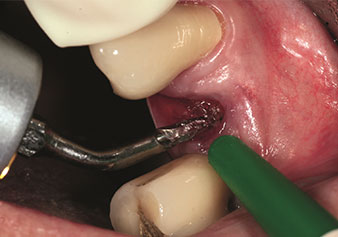

One application, which is often underestimated is the atraumatic extraction of tooth roots or root fragments in the scope of alveolar management. The fine periotomes, which are currently available in two versions (EX1 and EX2 from W&H), can also be used to remove teeth which have previously undergone special endodontic treatment or ankylosed roots with ease. This results in extraction alveoli where both the hard and soft tissue are fully intact as it is generally possible to avoid reflection.

This establishes the optimal basis for subsequent or immediate implant treatment (Figures 1 and 2 included with the kind permission of Dr Torsten Conrad, Bingen a. Rhein).

Photo: © Dr Torsten Conrad (Bingen a. Rhein)